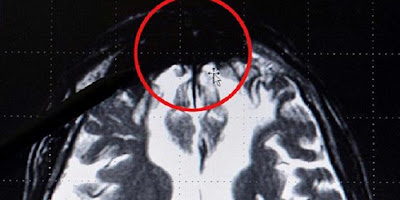

mengapa manusia bisa bertindak jahat? Karena ada bagian otak yang

membuat perilaku ini terjadi. Neurolog asal Jerman, Dr Gerhard Roth,

menemukan bagian otak tersebut. Tampak sebagai massa hitam dalam citra

sinar X, terletak di bagian depan bawah otak. Massa hitam didapatkan

pada hampir setiap pelaku kriminal.